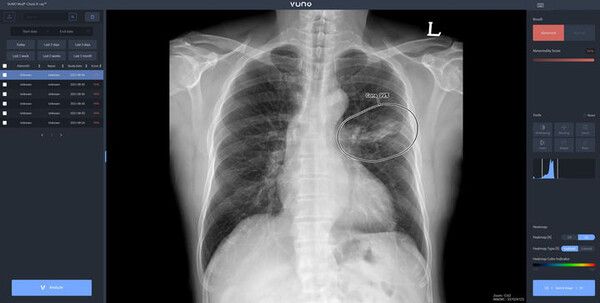

뷰노의 뷰노 메드 체스트 엑스레이는 흉부 엑스레이 영상의 주요 비정상 소견 여부와 위치 정보를 제공해 의료진의 판독을 보조한다.

AI가 흉부 영상을 분석해 주요 5개 소견(간질성 음영, 경화, 결절, 흉수, 기흉)에 대해 정상, 비정상 여부를 분석해 정보를 제공하고, 제공된 소견의 조합으로 폐암, 결핵, 폐렴과 같은 주요 폐질환의 진료를 보조한다.